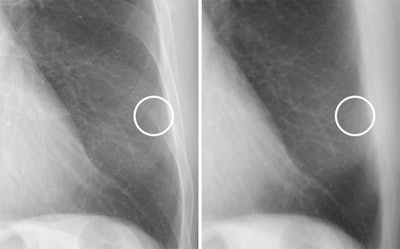

Doctors may be able to distinguish between calcified and noncalcified lung nodules on patient chest x-rays using a one-shot dual-energy subtraction (DES) technique, a group from Niigata University in Japan has found.

A team led by Motohiko Yamazaki, MD, compared soft tissue images obtained by a one-shot DES method compared with standard images alone and found the accuracy of five radiologists improved using the experimental technique.

Calcification is one of the most reliable indicators of whether or not solitary pulmonary nodules are benign. The accuracy of standard chest x-rays for detecting calcification is low, however, as small nodules may be obscured by overlapping structures such as the ribs, the authors explained.

DES is a technique based on acquiring two separate images from patients -- a low-energy and high-energy x-ray image -- which are then processed with structures that potentially obscure nodules in soft tissue subtracted from the reconstructed images. The recent development of flat panel digital detectors that can absorb both the low-energy and high-energy x-ray beams simultaneously has made a "single-shot" DES approach more feasible, they noted.

To evaluate the technique, the investigators identified 139 patients in whom both standard x-rays and one-shot DES images were acquired by the same system. The images included 155 nodules, of which 48 were calcified and 107 noncalcified. Five radiologists then interpreted whether or not the nodules were calcified using standard x-rays and then DES x-ray images.